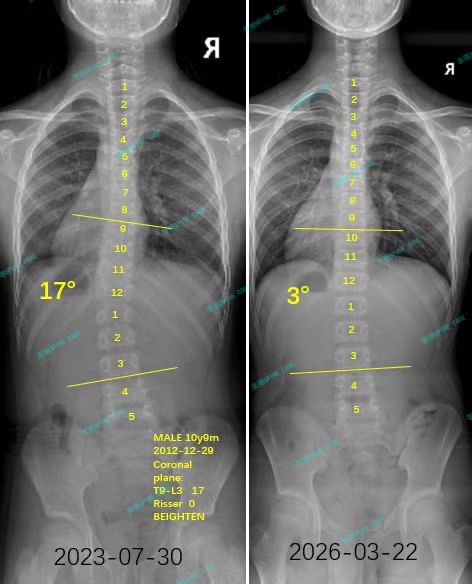

我是小俊,从17度到3度,这是我的脊柱侧弯修炼手册

案例主人:小俊 发现侧弯年龄:12岁 侧弯情况:Cobb角度17度

这一年我长高了10cm,训练也让我的体态看起来挺拔了许多,现在我整个人都笔笔直的,努力也没有白费。现在我的角度已经降到了3度,体态也明显改善了。杨医生说,康复就像爬山,偶尔会滑倒,但只要方向对了,总能登顶。而对我来说,TFboys的歌就是一路上的背景音乐,让我每一步都走得更有力量。感谢杨医生和他的团队的专业指导,没有杨医生团队的专业指导,我不知道我还要在脊柱侧弯康复中走多少弯路。

As expected, all my hard work paid off: the angle has now decreased to 3 degrees, and my posture has significantly improved.Dr. Yang explained that rehabilitation is akin to climbing a mountain; occasionally, you might slip, but as long as you stay on the right path, you will eventually reach the summit. For me, the songs by TFBoys have served as background music, giving me the strength to take each step forward. I am deeply grateful to Dr. Yang and his team for their professional guidance; without their expertise, I fear I would have taken many unnecessary detours in my journey toward recovery from scoliosis.